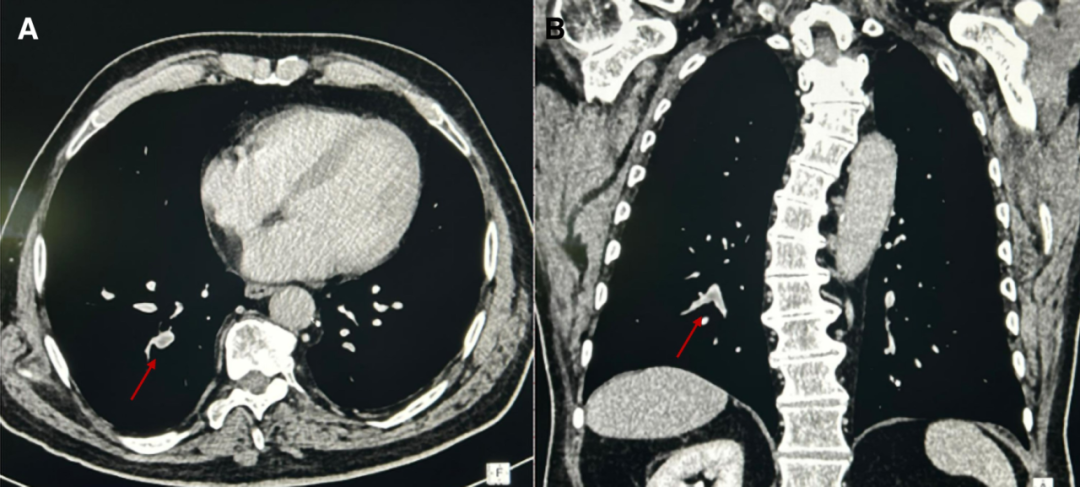

入院次日查D-二聚体3.72mg/L,CT肺动脉造影提示右下肺叶段支肺栓塞(图2A, B)。

图2计算机断层扫描肺血管造影显示肺动脉段支气管多发充盈缺损,符合肺栓塞(A和B,箭头;冠状面和矢状面)。CTPA,计算机断层扫描肺血管造影。